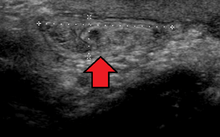

Inguinal

By far the most common hernias (up to 75% of all abdominal hernias) are the so-called inguinal hernias. Inguinal hernias are further divided into the more common indirect inguinal hernia (2/3, depicted here), in which the inguinal canal is entered via a congenital weakness at its entrance (the internal inguinal ring), and the direct inguinal hernia type (1/3), where the hernia contents push through a weak spot in the back wall of the inguinal canal. Inguinal hernias are the most common type of hernia in both men and women. In some selected cases, they may require surgery.